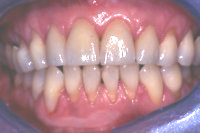

Die Abb. 1 bis 4 sollen als anschauliche Beispiele für gesunde und kranke Fundamente dienen.

Ein 31 Jahre alter Patient zeigt einen starke Zahnfleisch-Rückgang im Oberkiefer (Abb. 1 und 3) und wir beschliessen, diese Rezessionen zu behandeln.

Der Erfolg der Behandlung ist deutlich in den Abb. 2 und 4 zu sehen. Sehr augenfällig konnte die Situation um den Eckzahn im linken Oberkiefer verbessert werden (vergleiche dazu Abb. 3 vorher und Abb. 4 nachher).